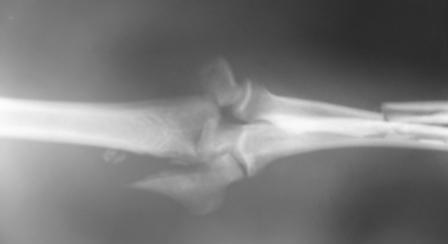

Больной Б. 43 лет, находится в клинике с диагнозом: Автотравма от 17.12.08 г. Открытый (3а) оскольчатый чрезмыщелковый перелом левой плечевой кости, закрытые оскольчатые переломы диафизов костей левого предплечья. Травму получил в Ленинградской области, доставлен в одну из районных больниц, где выполнена ПХО раны, начата АБ-терапия. Переведен к нам в клинику через сутки после травмы для оперативного лечения. Рана длинной около 8-10 см по задне-наружной поверхности плеча, без признаков воспаления. Планируется сначала выполнить остеосинтез локтевой кости пластиной DCP, затем остеосинтез плечевой кости по внутренней поверхности пластиной, по наружной - винтами, после остеосинтез лучевой кости LCP пластиной. Какие альтернативные методы лечения возможны в данной ситуации?